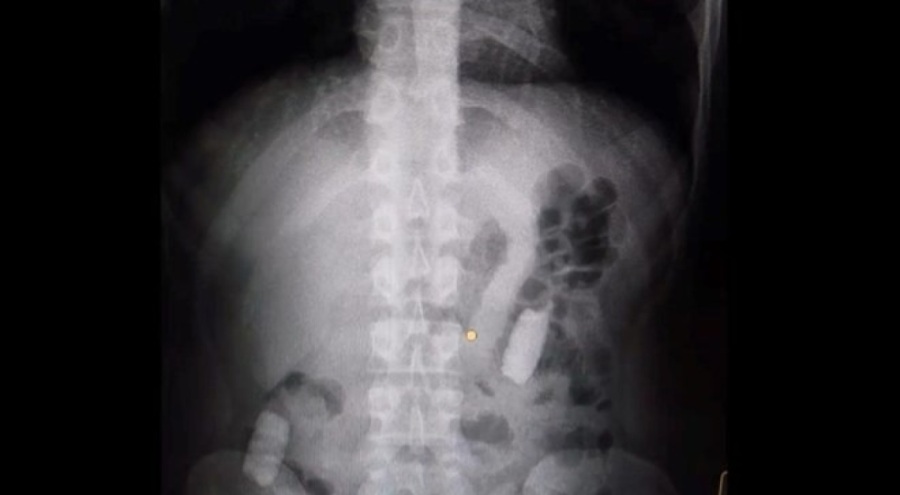

Kayseri'de, midesinde 1 kilo 134 gram afyon sakızı taşıyan M.R.B., polis tarafından yakalandı.

Gözaltına alınan M.R.B.'nin hastanedeki muayenesinde, midesinden 77 adet kapsül şeklinde 1 kilo 134 gram afyon sakızı çıkarıldı.